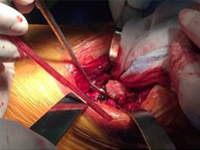

張某,男,50歲,因“左股骨骨不連”入院。植骨+PRP治療后8月完全愈合。

術中